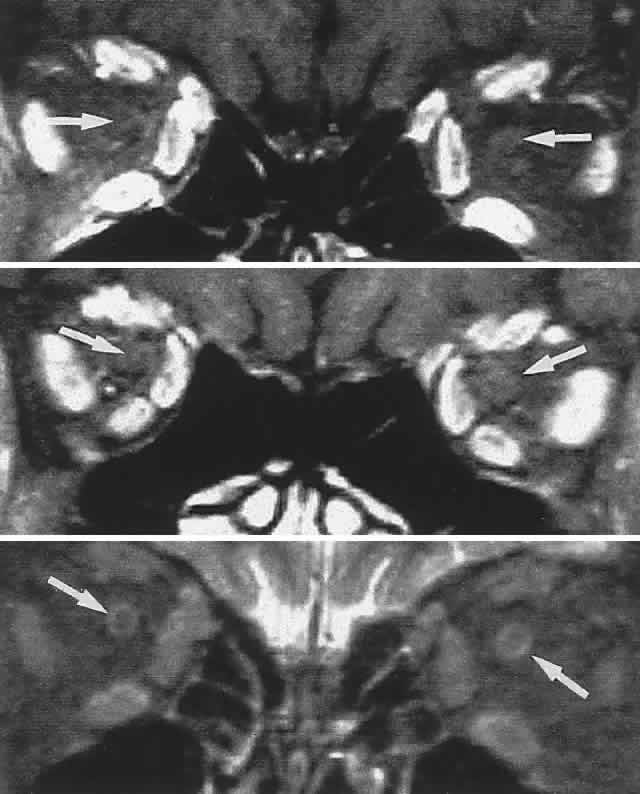

Graves' disease is the overwhelming single most common cause of single or multiple extraocular muscle thickening (Fig. 18; see also Volume 2, Chapter 12, Figs. 28 and 30); inflammatory myositis is considerably less frequent, and muscle metastases are quite rare. Passive congestive myopathy also accompanies arteriovenous shunts and lesions of the superior orbital fissure and cavernous sinus, where orbital venous return is obstructed. The capacity of CT to detect minor to moderate changes in muscle diameter is perhaps limited,70 and standardized A-scan ultrasonography seems more sensitive and practical.71

Fig. 18. CT scan in Graves' disease. Top. Axial section shows massively enlarged horizontal recti (M, medial) with packed apex. Bottom. Coronal section demonstrates enlarged medial (M), superior (S), and inferior (I) recti.